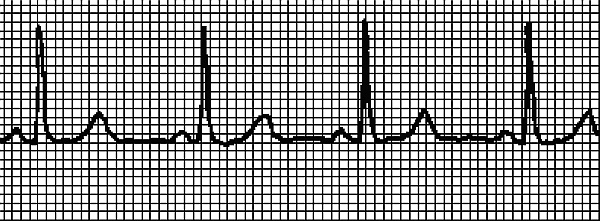

На рис. 2 записан нормальный синусовый ритм, на рис. 3 ритм при синусовой тахикардии. ЭКГ записывали у одного и того же человека сначала в состоянии покоя, затем после нагрузки. Даже не имея медицинского образования, можно понять, что существенных изменений в работе сердца не произошло – только учащение сокращений.

Рис. 2. Синусовый ритм

Рис. 3. Синусовая тахикардия